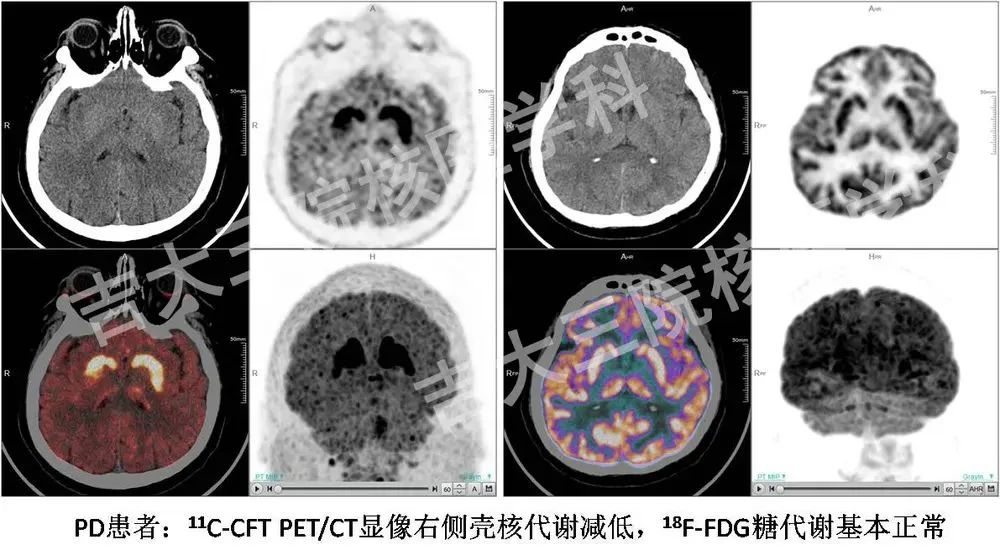

DAT是多巴胺能神經(jīng)元突觸前膜的一種膜蛋白,它可以在多巴胺能神經(jīng)元發(fā)放神經(jīng)沖動后把突觸間隙的多巴胺轉(zhuǎn)運回突觸前膜再利用或進一步分解,因此可以影響多巴胺的濃度。它的數(shù)量與多巴胺能神經(jīng)元數(shù)量,能夠直接反映突觸前膜多巴胺能神經(jīng)元的變化,比突觸后膜的多巴胺受體變化更早、更直接、更敏感。11C-CFT與突觸前膜DAT具有很高的親和力,可反映黑質(zhì)紋狀體通路多巴胺能神經(jīng)元功能,是 PD研究的特異性顯像劑。在應(yīng)用過程中,DAT顯像在PD的早期診斷方面已經(jīng)獲得臨床醫(yī)生的廣泛認(rèn)可,DAT正常時排除PD的準(zhǔn)確率可達97%,是PD早期診斷的最佳選擇。

18F-FDG是目前最常用的、最成熟的顯像方法。腦以葡萄糖作為最主要能源,因此葡萄糖代謝可反映腦內(nèi)神經(jīng)元的活性。研究表明,PD與非典型PD綜合征患者不同腦區(qū)的葡萄糖代謝存在差異,因此可利用葡萄糖代謝成像進行鑒別診斷。典型PD腦內(nèi)基底節(jié)葡萄糖代謝相對保留,而雙側(cè)額葉前運動及輔助運動區(qū)呈低代謝。同時,在新的圖像處理技術(shù)、智能的自動化診斷程序幫助下,18F-FDG PET/CT顯像能夠在PD早期診斷中發(fā)揮更大的作用。

聯(lián)合DAT及FDG功能影像學(xué)手段有利于PD的早期診斷、鑒別診斷,彌補單一檢查的不足,從多個角度評估病理生理變化,對病情進行全面評價。目前,11C-CFT PET/CT顯像已在我國北京301醫(yī)院、上海華山醫(yī)院等多家三級甲等醫(yī)院展開應(yīng)用,在早期診斷PD方面取得了令人鼓舞的臨床效果。